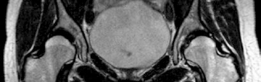

التصوير المقطعي والرنين المغناطيسي

بالإضافة إلى الأشعة السينية، تُستخدم تقنيات تصوير أكثر تقدماً لتوفير تفاصيل أدق حول المفصل:

التصوير بالرنين المغناطيسي (MRI) / تصوير مفصل الورك بالرنين المغناطيسي (MR Arthrography): يوضح سلامة الشفا الحُقي، وحالة الغضروف المفصلي، ويمكن أن يحدد أي أمراض أخرى داخل المفصل مثل الأجسام الحرة أو تمزقات الرباط المدور، مما يساعد في توجيه الإجراءات التنظيرية المصاحبة. هذه التقنيات ضرورية لتقييم الأنسجة الرخوة التي لا تظهر بوضوح في الأشعة السينية أو الأشعة المقطعية.

يُعد التخطيط الدقيق قبل الجراحة أمراً بالغ الأهمية لتحقيق أفضل النتائج وتقليل المضاعفات. باستخدام برامج القوالب الرقمية، يمكن للجراحين محاكاة إعادة توجيه التجويف الحُقي، وتحديد الاتجاه الأمثل للدوران والترجمة المطلوبة لتحقيق التغطية المطلوبة وتقليل الانحشار. يساعد هذا في التنبؤ بطول المسمار اللازم ومساره للتثبيت. كما أن مراعاة إزاحة رأس الفخذ-العنق مهمة أيضاً لمعالجة أي انحشار فخذي حُقي (Femoroacetabular Impingement - FAI) متزامن.